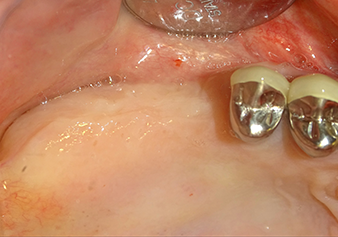

To move the augmentation material in the direction of the maxillary sinus atraumatically, the implant was inserted very slowly by hand (Fig. 9). In the process, the membrane was pushed in the cranial direction once again. After two months, the surgical site healed without irritation. Six months later, the x-ray check showed a significant increase in opacity as an indication of ossification (Fig. 10). The prosthetic restoration was carried out with a metal-ceramic crown.

The x-ray check shows a largely homogeneous peri-implant hard tissue structure

Fig.10: A good six months later, after the definitive crown had been incorporated, the x-ray check shows a largely homogeneous peri-implant hard tissue structure.